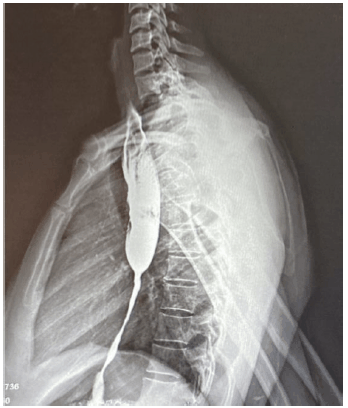

Paciente sexo feminino, 40 anos, procura atendimento com quadro de disfagia progressiva, no momento para líquidos, dois anos após ingesta de soda cáustica. Submetida à esofagografia, como mostra a imagem a seguir.

Em relação ao caso, assinale a melhor conduta endoscópica.